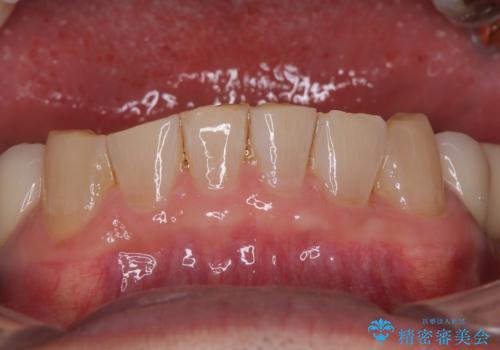

- 下顎両側の欠損と上顎前歯のデコボコを気にして来院された患者様です。

デコボコは今まで気にせずにいたそうですが、奥歯の欠損改善を機に、矯正治療に興味があるので、相談したいとのことでした。

奥歯に欠損が多く、矯正治療はやや難航することが予想されますが、患者様の希望もあり、上顎左右小臼歯を1本ずつ抜歯し、ワイヤー装置にて矯正治療を行うこととしました。

矯正歯科治療を行うに当たり、痛みや違和感を感じている歯の根管治療を行い、矯正治療中にインプラント埋入し、補綴治療と矯正治療を同時に終了できるように進めて行くこととしました。